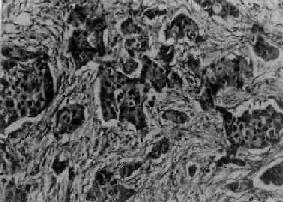

图13-27 乳腺髓样

细胞排列成片团状,间质少